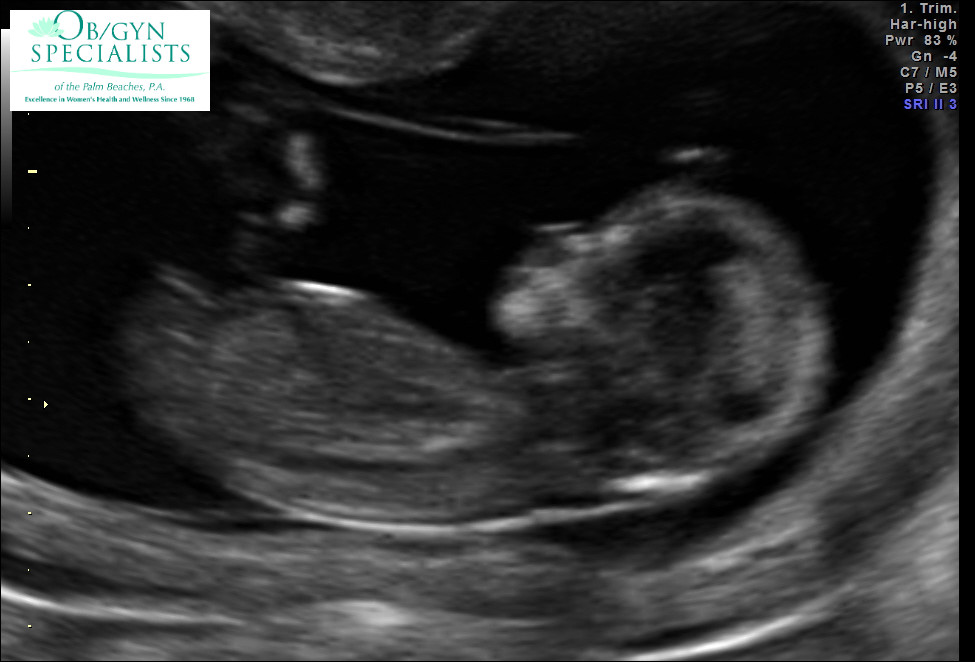

Any guesses for me guys?? I have been staring at this thing for two days. I just can not tell.

Girl x

Yes I would go girl too

Girl.

Long and flat...I'm going to guess girl. GL!

Girly guess!

looks like there is a little bump on the nub so at this stage I'm no sure! 50/50 guess from me.....

Agreeing with Wilma but I'm leaning boy:)